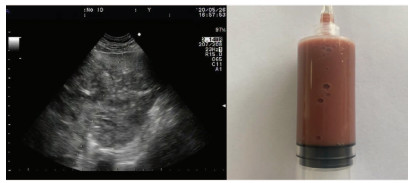

Pyogenic liver abscess caused by Streptococcus mitis: A case report

Likui FENG, Guosheng DU

2021, 37(2): 408-410. DOI: 10.3969/j.issn.1001-5256.2021.02.033

Abstract(1087) HTML (561) PDF (2226KB)(60)

Abstract: